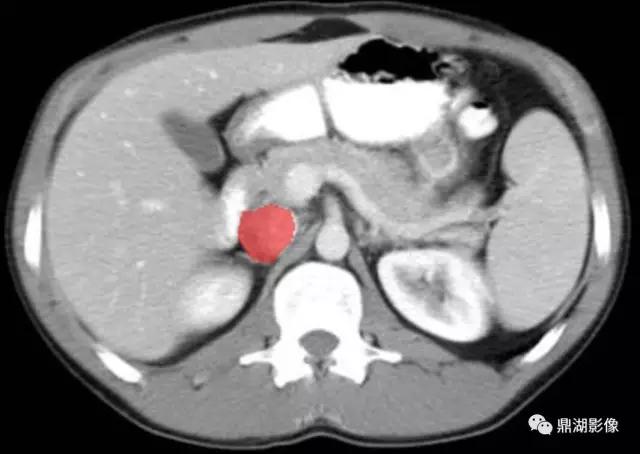

肠系膜上动脉(Superior Mesenteric Artery)

肠系膜上静脉(Superior Mesenteric Vein)